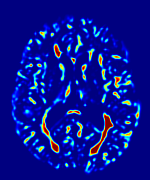

We observed that memberships predicted with an FC layer result in more false positives compared to a fully convolutional network. An example is shown in Fig. 2, where lesion memberships are generated from MPRAGE and FLAIR using the proposed model of convolutional pathways and a comparable model where the last convolutional pathway after concatenation (see Fig. 1) is replaced with a FC layer predicting voxel-wise memberships. The membership image generated with an FC layer, although being close to inside the lesions, has high values () in the left and right frontal cortex where the FLAIR image shows some artifacts. However, the membership obtained with the proposed method shows relatively low values near the frontal cortex.

With FC layer, voxel-wise predictions are performed for each voxel on a new image. Therefore the prediction time for the whole image comprising millions of voxels can take some time even on a GPU, as mentioned in Wachinger et al. (2017). In contrast, with fully convolutional prediction, lesion membership estimation of a mm3 MR volume of size takes only a couple of seconds. Note that although patches are used for training, the final trained model contains only convolution filters and does not depend in any way on the input patch size. Therefore during testing, the lesion membership of a whole 2D slice, irrespective of the slice size, is predicted at a time by applying convolutions on the whole slice. Without an FC layer, the images need not be decomposed into sub-regions, e.g., Kamnitsas et al. (2017). Consequently, there is no need to employ membership smoothing between sub-regions. In addition, since the training memberships, generated by Gaussian blurring of hard segmentations, are smooth, the resultant predicted memberships are also smooth (Fig. 2 last column).

Patch size is another important parameter of the network. In computer vision applications such as object detection, usually a whole 2D image is used as a feature. However, full 3D medical images can not typically be used because of memory limitations. Fig. 4 shows examples of lesion memberships obtained with different sized 2D patches. As the patch sizes increases, the false positives that are mostly observed in the cortex tend to decrease. Fig. 5 shows a plot of Dice and LFPR with various patch sizes, ordered from left to right according to their increasing size. Note that smaller patches ( to ) produced significantly lower Dice and higher LFPR compared to other patches (), as seen from the memberships in Fig. 4. Also some of the highest Dice and lowest LFPR were observed for patches with large in-plane size, i.e., , , and . It was observed in Fig. 5 that there is no significant difference between Dice coefficients for , , or , but LFPR of both and are significantly lower than that of (). We chose as the optimal patch size. Other choices of smaller and patches (not shown) yielded worse results. Note that although training was performed with different patch sizes, the memberships were generated slice by slice, as the trained model consisted only of convolutions and did not need any information about patch sizes.